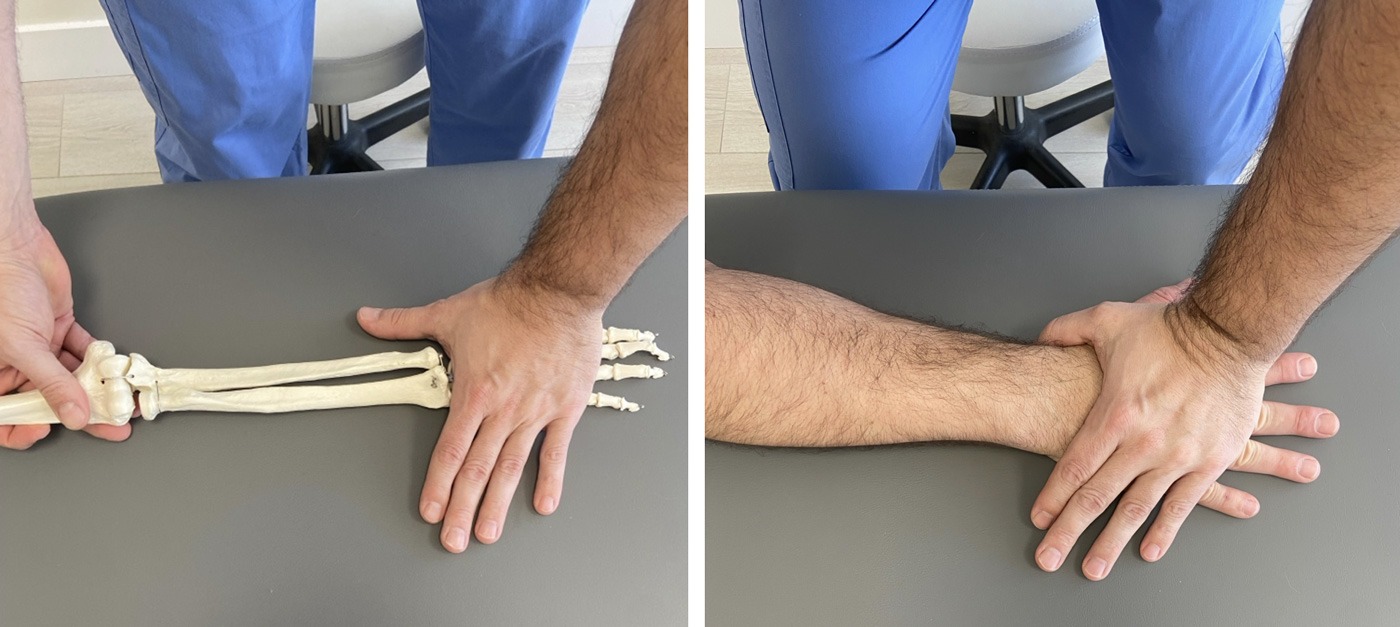

2. Estiramiento con la mano apoyada en una superficie plana y estable

Vamos a apoyar el dorso de la mano sobre la que queremos trabajar en la mesa.

En este caso debemos de ser especialmente cuidadosos con no apoyar demasiado peso sobre la mano porque puede resultar doloroso.

Utilizaremos la mano contraria para fijar y estabilizar la mano que queremos estirar lo más cerca que podamos de la muñeca sin bloquear el movimiento de esta.

Y elevaremos el codo de la mesa hasta que consigamos generar tensión y estiramiento sobre la musculatura extensora de la muñeca situada en la cara dorsal del antebrazo.